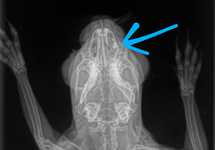

- Radiography of underlying structures: often teeth, skull, limbs, or chest.

- CT scan to examine and determine the extent of internal abscesses and facial abscesses.